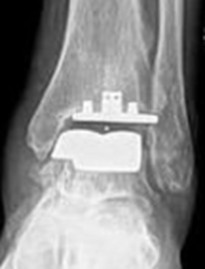

Moderne Sprunggelenksprothesen bestehen meist aus mehreren Komponenten aus Metall und einem beweglichen Kunststoffkern. Sie ahmen die natürliche Bewegung des Gelenkes nach und sollen eine möglichst gleichmäßige Belastung ermöglichen.

Die Abbildungen zeigen eine Endoprothese des oberen Sprunggelenkes. Sie ist ein sogenannter Oberflächenersatz (Resurfacing). Dieses Implantat wird zementfrei eingesetzt.